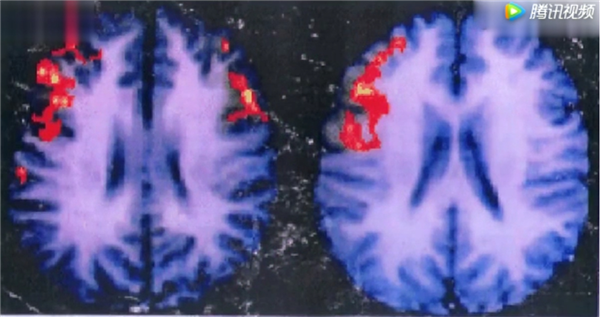

我们大脑中间有一个连接左右脑的神经丛---胼胝体,女人的胼胝体要比男人的粗壮,女人在思考问题的时候,同时使用两边的脑子来处理同一个问题,如果用脑电图来测试的话,就能测试到女性在思考问题的时候,电信号比较多。这也就是说,女性在思考问题的时候可以分别用不同的观点来看问题。男人呢,大多只使用单侧脑思考。 所以,比较单一,也比较执着。